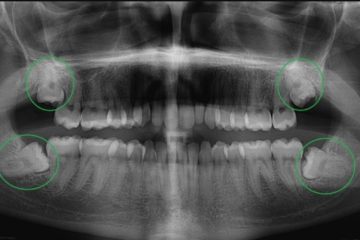

Khi nào nên nhổ răng sữa cho trẻ?

Quá trình thay răng sữa để nhường chỗ cho răng vĩnh viễn là một cột mốc quan trọng trong sự phát triển của trẻ. Tuy nhiên, không phải lúc nào răng sữa …